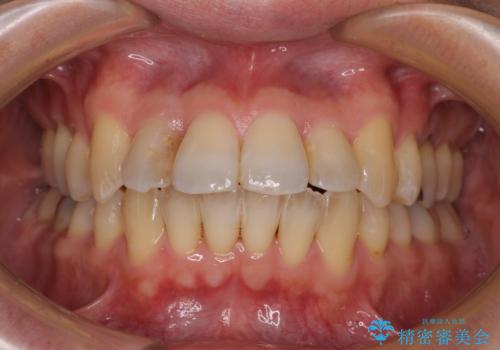

オープンバイトでかみにくい インビザラインによる矯正治療

- 前歯の上下スペースによる食べにくさを気にして来院された患者様です。

インビザラインにより上下の前歯の隙間を閉じていくこととしました。

上下の奥歯を圧下させるようにすることで、前歯を接触させるように計画しました。

上下の隙間に舌が入り込むことがオープンバイトの原因であったため、舌の筋肉のトレーニングも並行して行い、後戻りの抑制を図りました。